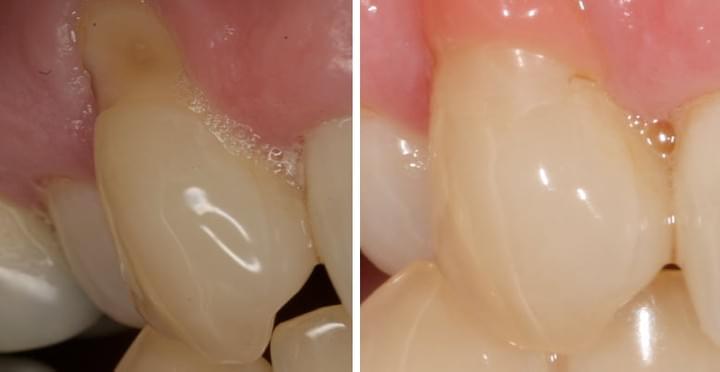

- Consequences 1: Gum recession, exposed roots and tooth sensitivity - Gum recession can happen with abrasive wear. When gums recede, roots of the teeth are exposed and they can be very sensitive to temperature and pressure. Continuous hard brushing can exaggerate the sensitivity and makes it harder to be managed conservatively.  - Consequences 2: Tooth decay and crown fracture - When more roots wear away with ongoing hard brushing, notches on roots along the gum line become deeper and bigger. Brushing can become difficult and the risk of tooth decay increases. Besides, the strength of the tooth along the notches becomes weaker, and abfraction can happen. The crown can potentially break and tooth removal may be required.  - Consequences 3: Aesthetics - With exposed roots and the present of abrasive wear, your appearance can be compromised because of their shapes and a more yellowish colour. They can be challenging to manage with conservative treatment and other restorative options can be expensive and difficult.